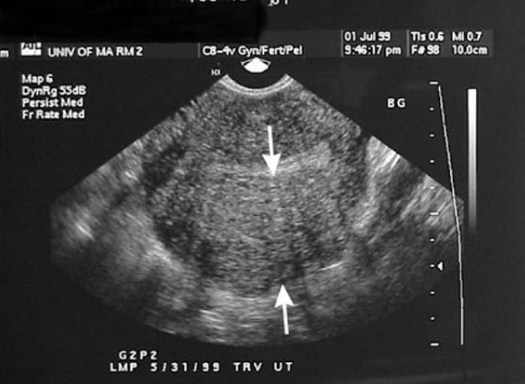

Kedua, adalah Uterine Fibroids atau Fibroid rahim yang dapat membuat rahim wanita membesar. Dalam penelitian telah menunjukkan jika sekitar 40-50% wanita menderita Fibroid dalam rahim. Fibroid disini digambarkan pada pertumbuhan non-kanker di rahim. Biasanya terjadi dalam usia subur.

Kondisi ini terjadi saat jaringan yang biasanya garis rahim mulai tumbuh di dalam dinding otot rahim. Adenomyosis kemudian adalah istilah medis untuk kondisi tersebut, dan penyebab paling umum dari rahim membesar. Pada umumnya penebalan rahm terjadi pada wanita usia 30an yang telah memiliki anak.